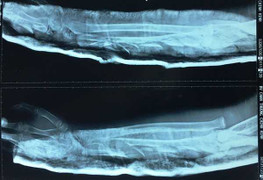

Bác sĩ khẩn cấp truyền 2,5 lít máu nối lại tay phải gần đứt lìa, cứu ngón tay trái hoại tử, phục hồi chân liệt cho người đàn ông bị chém trọng thương, sốc mất máu.

Đang đứng bán mía cùng mẹ và anh trai ở chợ, anh Vương bất ngờ bị nhóm côn đồ vác kiếm lao đến chém tới tấp vào người khiến anh gục tại chỗ.